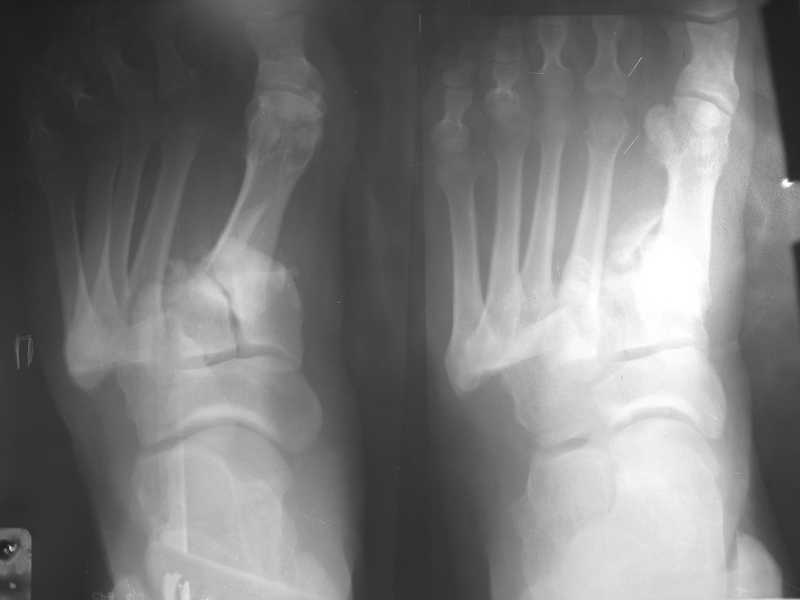

Здравствуйте , уважаемые коллеги. Обратился пациент, мужчина 42лет. для дальнейшего

лечения. Травма 11.09., ДТП.

15.09 проведено оперативное лечение (Блокирующий стержень левого

бедра - статическая система. Открытое вправление вывиха в суставе

Лисфранка и фиксация мет. фиксаторами.)

1.на снимке №3 (стопа в боковой проекции с винтами) складывается впечатление о сохраняющемся подошвенном подвивихе в суставе Лисфранака или это искажение при обработке фото?

Вправление и фиксация лисфранка было там же, на оригинальных снимках подвывиха нет.